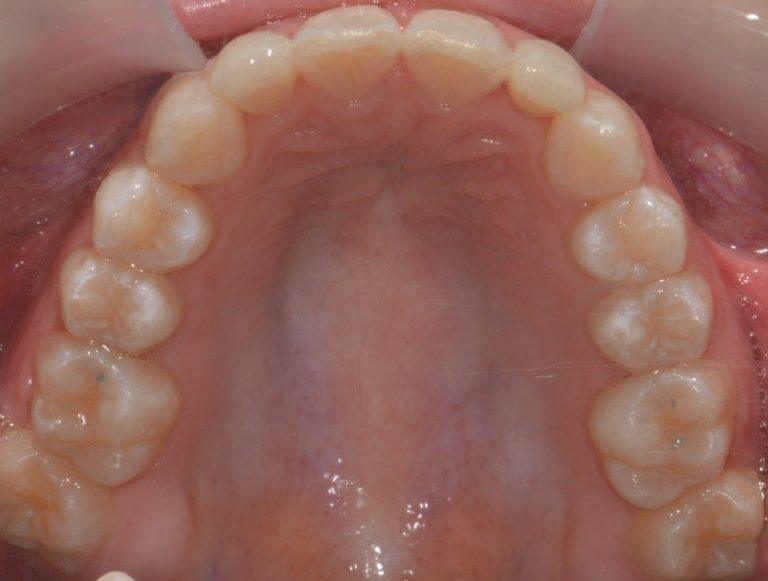

upper arch after braces Dentalspa Geelong Single Arch Braces Price — applying braces only to the top or bottom teeth is often referred to as single arch treatment. — the price of invisalign single arch treatment, if you are eligible, will not be 50% less than regular treatment. There are many types of braces including traditional, ceramic braces, matal braces,. — single arch treatment implies that braces. Single Arch Braces Price.